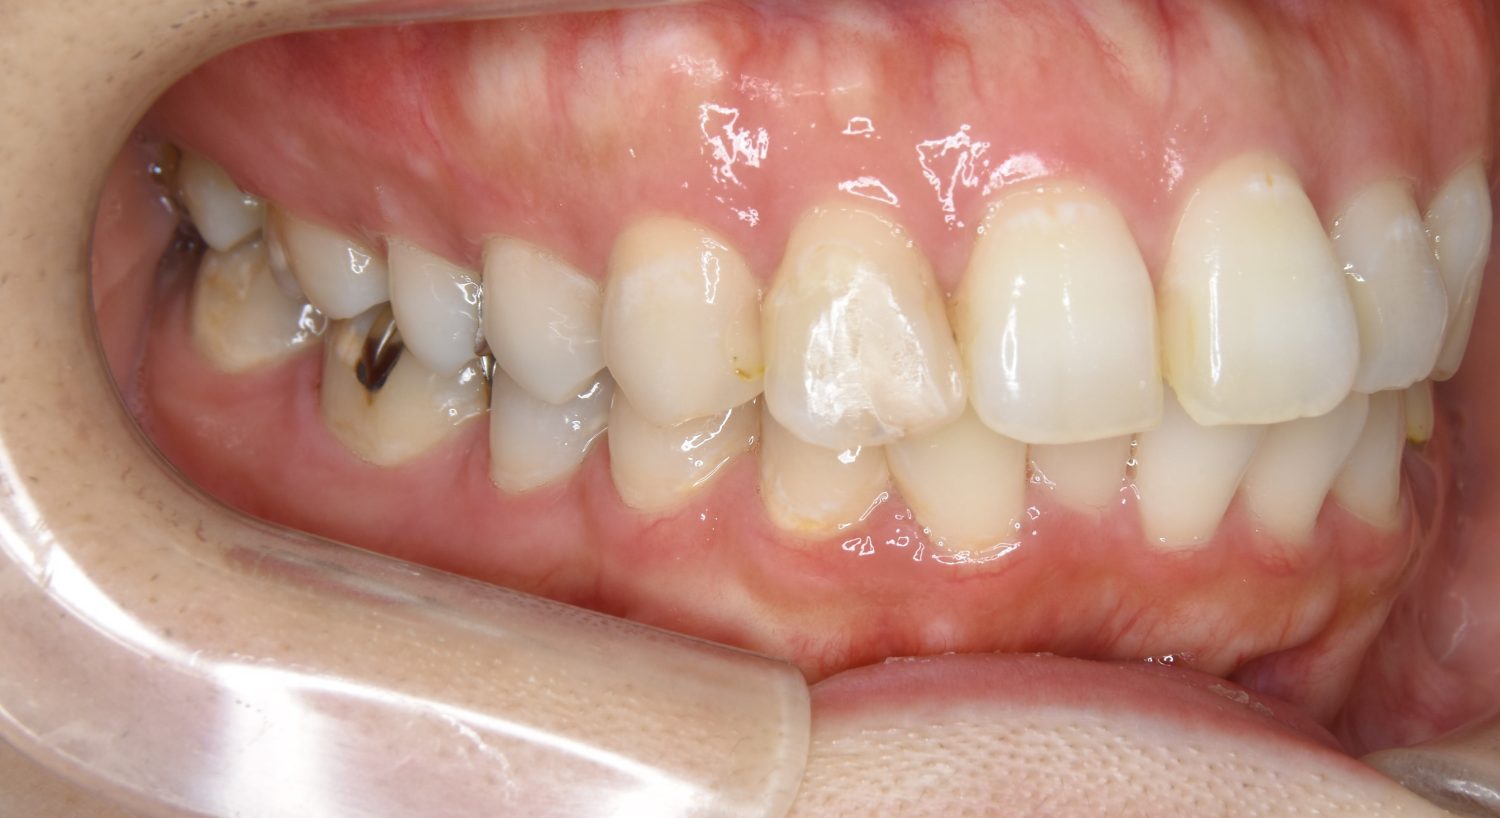

Before

上下の前歯が開いており前歯では全く噛めていない状態でした。臼歯の圧下を行うことで機能面のみでなく審美面も改善しました。